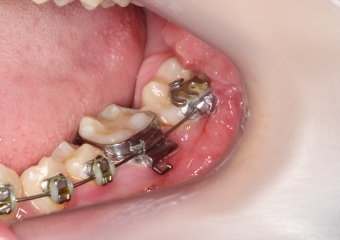

Elementos 37 e 47, respondendo bem ao tracionamento - Clínica Cliniface

Elementos 37 e 47, respondendo bem ao tracionamento